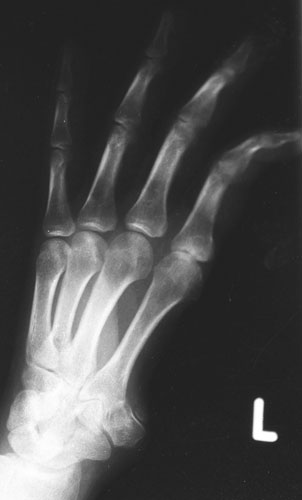

Zimbabwe A spear shot through a man’s hand. Photograph: Courtesy Hermann Vogel